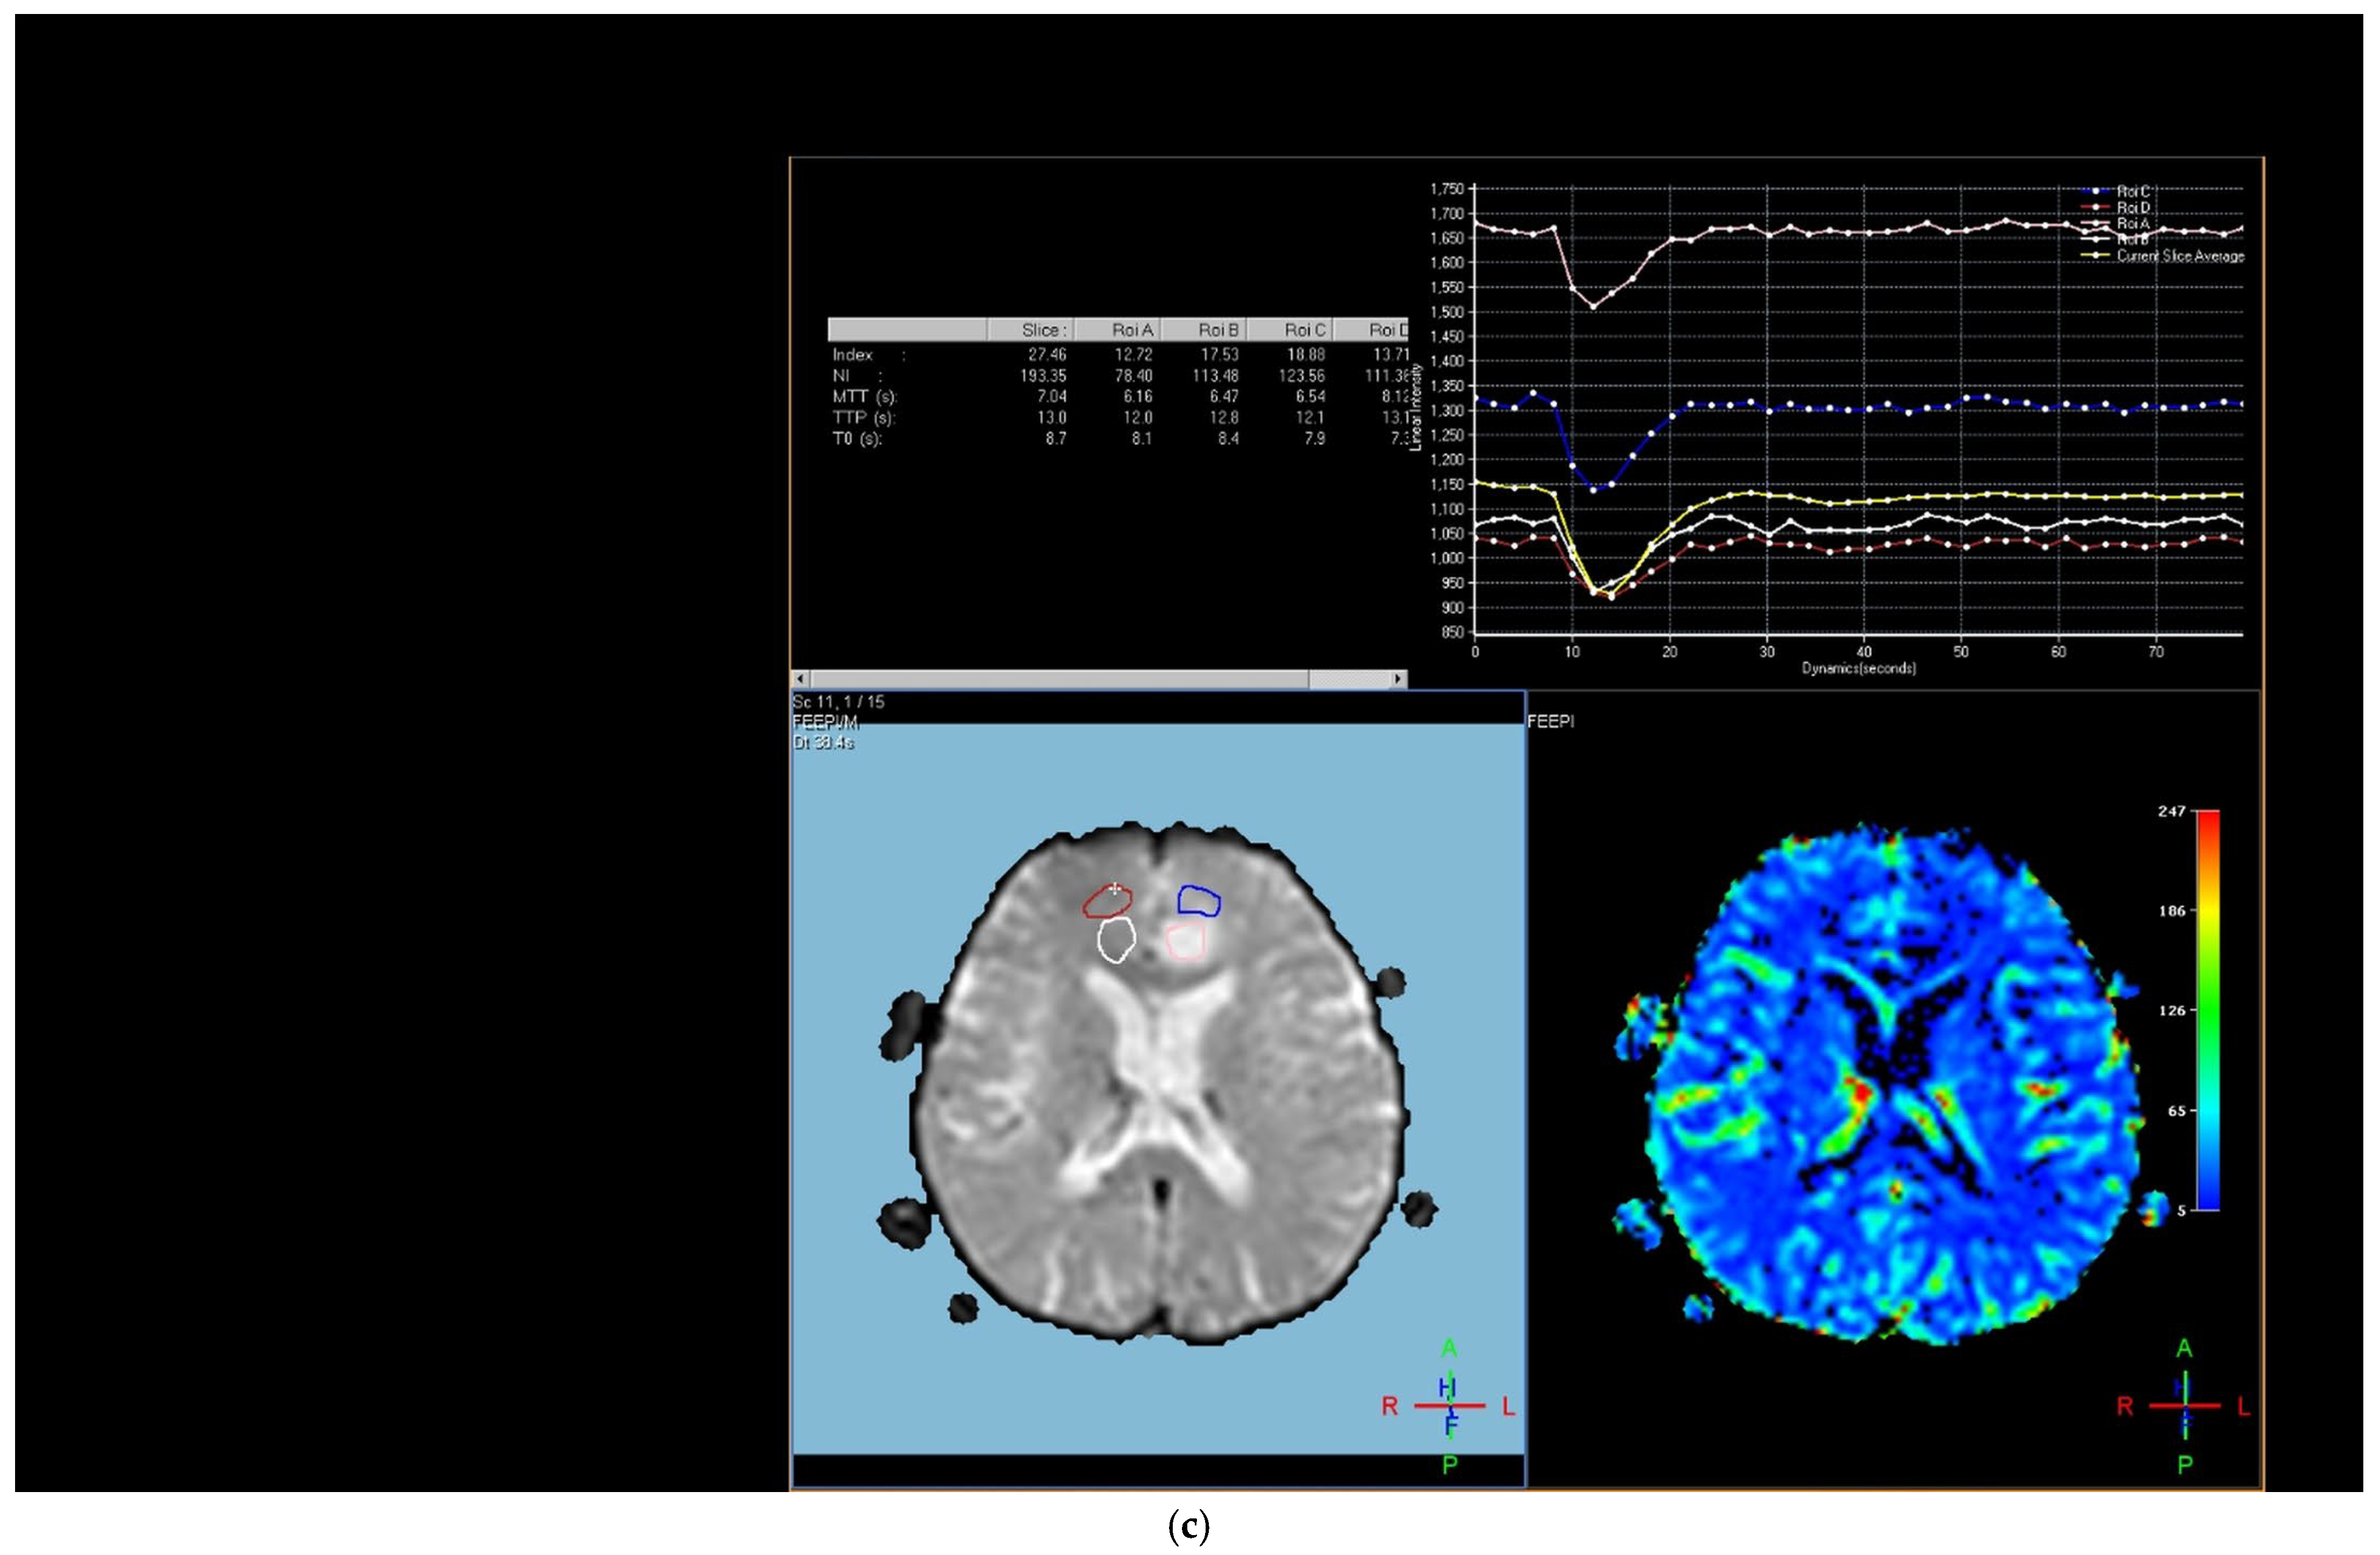

Figure 3. Brain magnetic resonance imaging (MRI) of a 51-year-old male histopathologically diagnosed with glioblastoma. (a) Increased signal on T2-weighted image with peritumoral edema, (b) peripherally enhanced right frontal subcortical mass on post-contrast axial T1-weighted image, and (c) hyperperfusion with a rCBV of 1.5 in perfusion-weighted imaging (Pink ROI is from tumor and white ROI is from contralateral parenchyma).

We further performed analyses based on the grade of the glial tumors. Tumoral rCBV values of high-grade glial tumor patients were significantly higher than those with low-grade glial tumors (Figure 3) (p = 0.009). Tumoral and peritumoral rCBV values of patients with high-grade glial tumors were higher than those with brain metastases (Figure 3) (p < 0.001 and p = 0.001). For the lung cancer types, although statistically not significant, there was a trend toward higher values in tumoral rCBV of high-grade glial tumors than small-cell lung cancer patients (p = 0.068). Tumoral and peritumoral rCBV medians of high-grade glial tumor patients were significantly higher than those of non-small-cell lung cancer patients (p < 0.001 and p = 0.003). While the median rCBV in both the tumoral and peritumoral regions of patients with high-grade glial tumors exceeded that of patients with breast cancer, the difference did not attain statistical significance (p = 0.311 and p = 0.053). Tumoral and peritumoral rCBV values were higher in patients with high-grade glial tumors compared to metastasis from miscellaneous organs (p < 0.001 and p = 0.003).